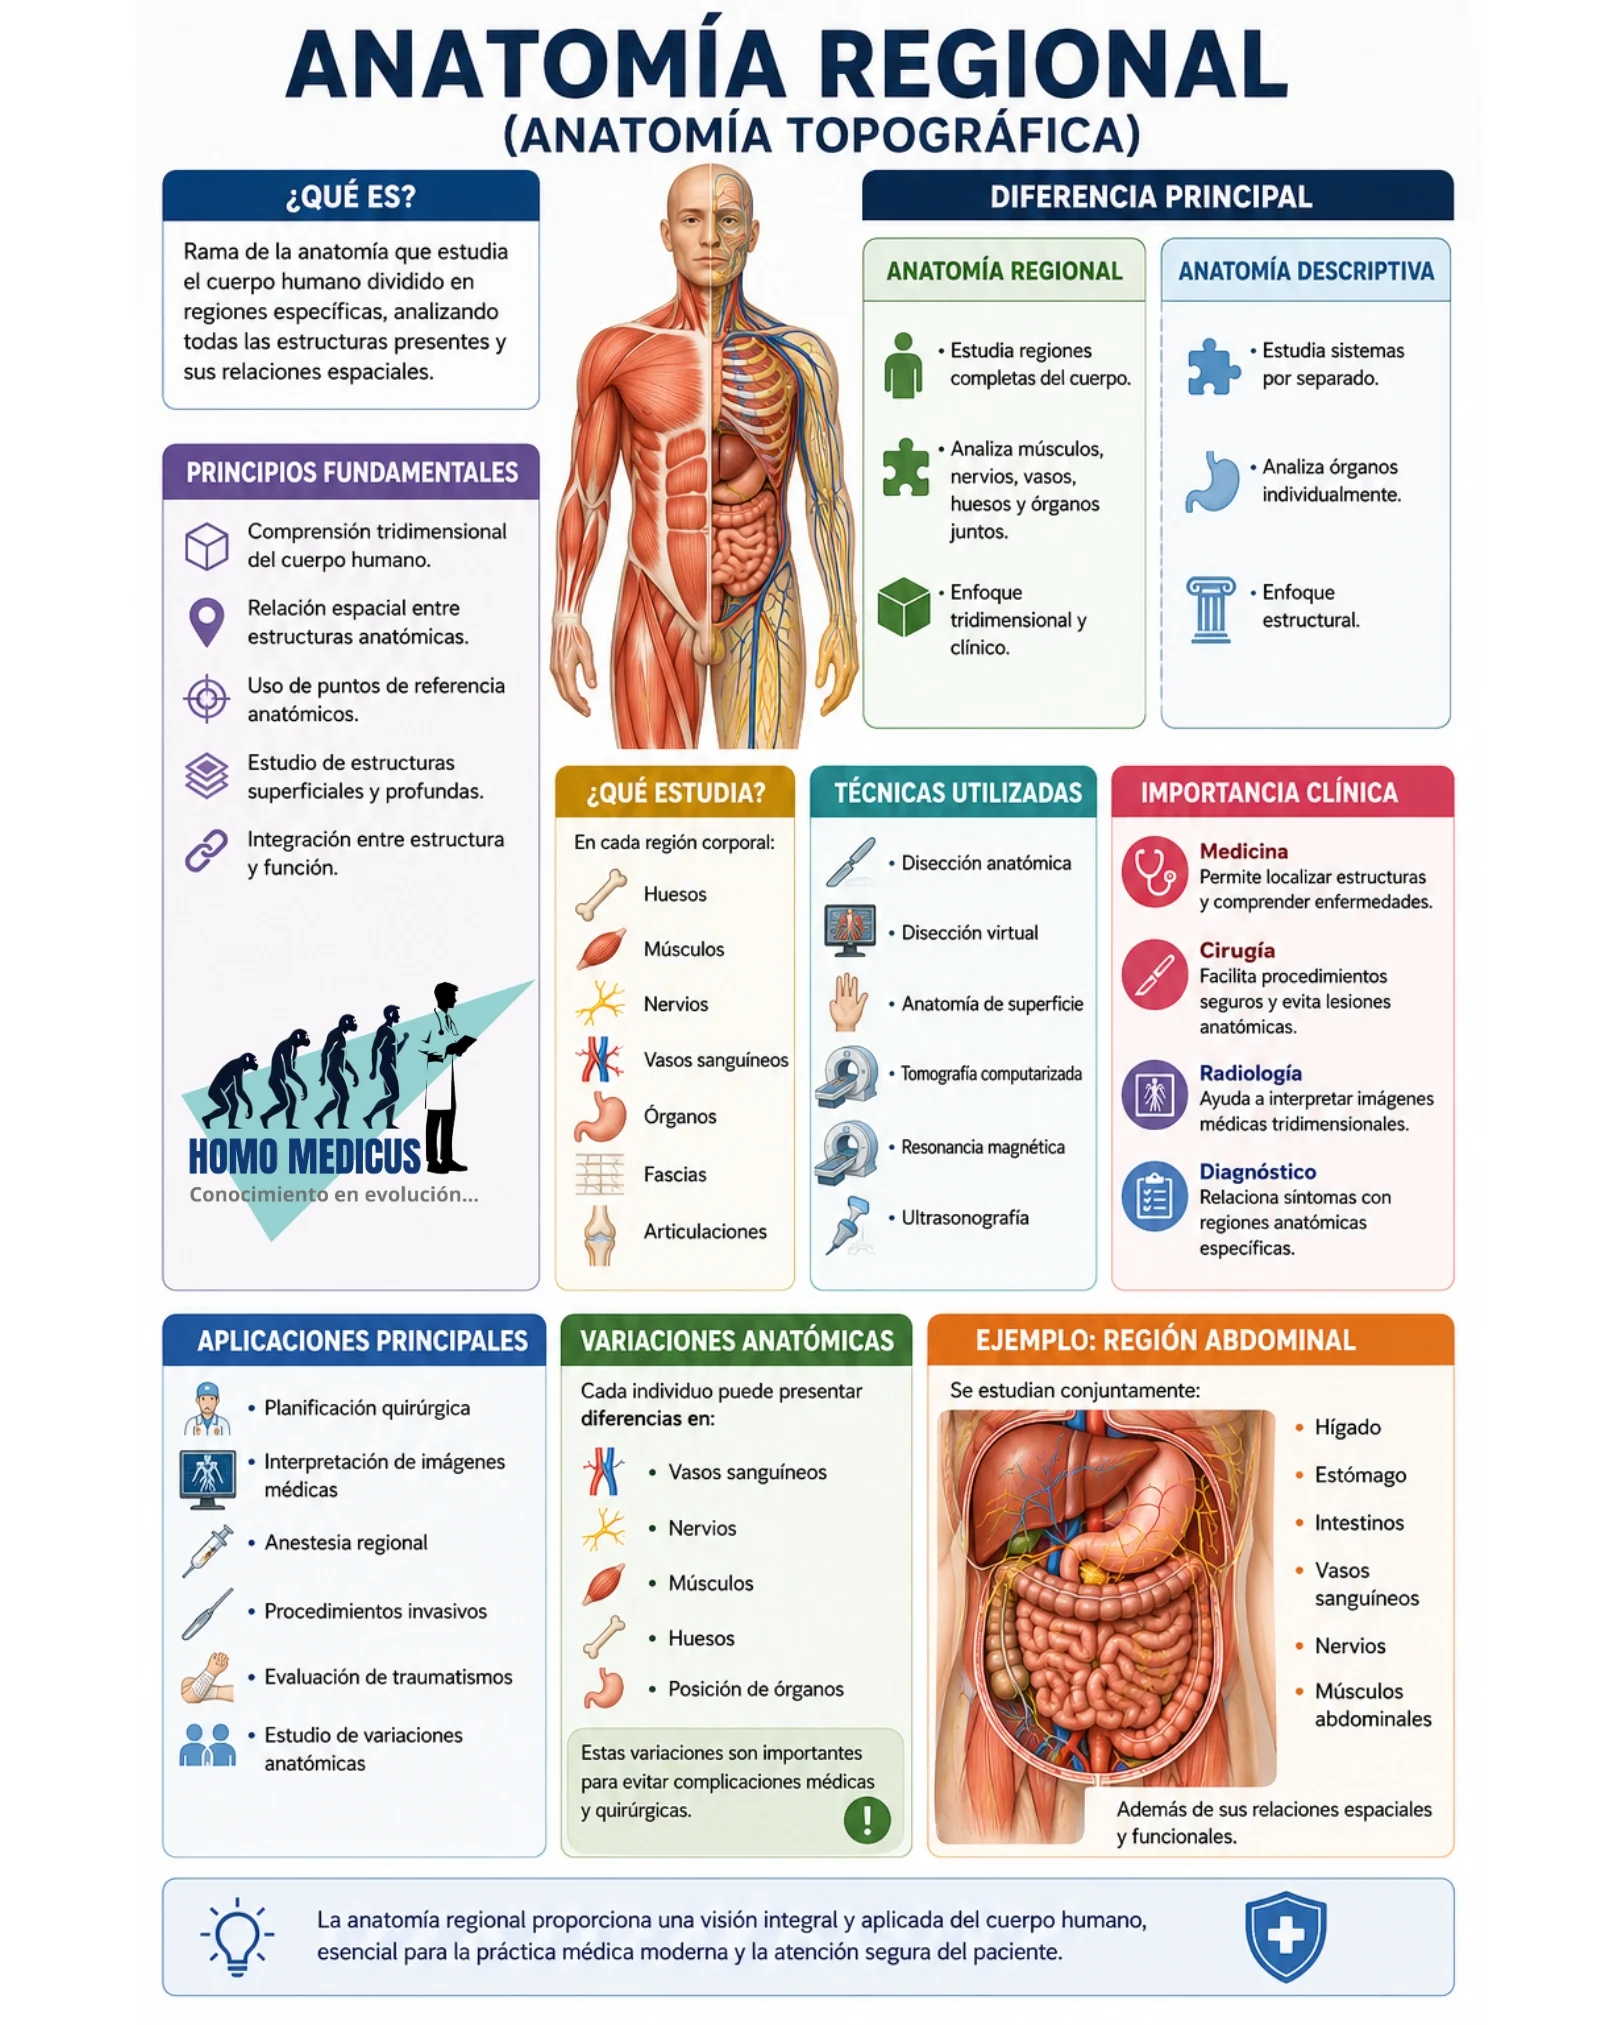

La Anatomía Regional, denominada también anatomía topográfica, constituye una disciplina fundamental dentro de las ciencias biomédicas porque permite comprender el cuerpo humano como una organización tridimensional integrada, en la cual cada estructura mantiene relaciones espaciales, funcionales y clínicas con los elementos circundantes. Su importancia deriva de que el organismo no funciona como un conjunto aislado de órganos independientes, sino como regiones anatómicas donde músculos, vasos sanguíneos, nervios, fascias, huesos y vísceras interactúan constantemente dentro de espacios delimitados y dinámicos. La anatomía regional estudia precisamente estas relaciones espaciales y topográficas, proporcionando una visión integral indispensable para la práctica médica, quirúrgica y radiológica.

A diferencia de la anatomía sistemática o descriptiva, que organiza el estudio del cuerpo por sistemas como el nervioso, muscular o cardiovascular, la anatomía regional analiza cada territorio corporal como una unidad anatómica compleja. Esto implica estudiar simultáneamente todas las estructuras presentes en una región determinada, incluyendo sus límites, planos, trayectos, irrigación, inervación y relaciones profundas y superficiales. Este enfoque reproduce de manera mucho más precisa la realidad clínica observada en pacientes vivos, donde las enfermedades, traumatismos y procedimientos quirúrgicos afectan regiones completas y no sistemas aislados.

La razón científica principal por la cual la anatomía regional posee tanta relevancia es que el cuerpo humano está organizado topográficamente. Cada órgano ocupa una posición específica mantenida por relaciones biomecánicas, fasciales, vasculares y nerviosas. El hígado, por ejemplo, no puede comprenderse únicamente como un órgano digestivo; debe analizarse en relación con el diafragma, el estómago, el duodeno, la vena cava inferior, el peritoneo y la vía biliar. Estas relaciones determinan la propagación de infecciones, hemorragias, tumores y traumatismos. La anatomía regional permite entender cómo una alteración localizada puede afectar múltiples estructuras vecinas debido a la continuidad espacial de los tejidos.

El fundamento metodológico de la anatomía regional se basa en la identificación de regiones anatómicas delimitadas por referencias óseas, musculares y superficiales. Estas referencias constituyen puntos de orientación esenciales porque permiten correlacionar estructuras visibles externamente con elementos profundos no observables directamente. La anatomía de superficie adquiere aquí enorme importancia clínica, ya que posibilita localizar vasos arteriales, trayectos nerviosos, órganos internos y puntos de acceso quirúrgico mediante referencias palpables. La precisión de estas relaciones es indispensable para procedimientos como punciones vasculares, anestesias regionales, drenajes, biopsias y exploraciones físicas.

La anatomía regional también posee enorme importancia porque reproduce fielmente las condiciones reales observadas durante la cirugía. En el entorno quirúrgico, los cirujanos no encuentran órganos aislados, sino capas anatómicas superpuestas organizadas regionalmente. La disección anatómica regional enseña la disposición secuencial de piel, tejido celular subcutáneo, fascias, músculos, vasos y órganos, permitiendo comprender los planos anatómicos de abordaje y separación tisular. Esta comprensión es esencial para reducir daño quirúrgico, preservar estructuras nobles y optimizar la recuperación funcional del paciente.

Otro aspecto fundamental es que la anatomía regional constituye la base de la interpretación radiológica moderna. Técnicas como tomografía computarizada, resonancia magnética y ultrasonografía generan imágenes seccionales del cuerpo organizadas espacialmente. La correcta interpretación de estas imágenes requiere comprender relaciones tridimensionales complejas entre múltiples estructuras anatómicas simultáneamente. La radiología moderna depende directamente del conocimiento topográfico porque las imágenes diagnósticas muestran regiones anatómicas completas y no sistemas aislados.

La existencia de variaciones anatómicas representa otra razón crucial para el estudio regional. El cuerpo humano presenta diferencias morfológicas normales entre individuos respecto a trayectos vasculares, distribución nerviosa, tamaño muscular y configuración ósea. Estas variaciones pueden modificar significativamente procedimientos diagnósticos y terapéuticos. Una arteria aberrante, un nervio accesorio o una disposición inusual de órganos puede aumentar el riesgo quirúrgico si no es reconocida previamente.

Las variaciones anatómicas poseen importancia clínica porque pueden alterar síntomas, modificar patrones de dolor referido y cambiar la presentación radiológica de enfermedades. Además, algunas variaciones condicionan susceptibilidad diferencial a compresiones neurovasculares, hernias o lesiones traumáticas. Por esta razón, la anatomía regional no se limita a describir configuraciones ideales, sino que estudia rangos de variabilidad anatómica presentes en la población humana.